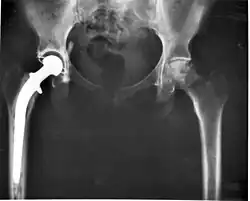

Biomateriais e desenvolvimento de próteses

Determinadas pessoas, que devido a acidentes, doenças degenerativas ou a deficiências físicas, podem precisar de próteses. Estas próteses têm que ser adequadas à função a que se destinam. Para isso são desenvolvidos novos materiais mais compatíveis com o corpo humano. Estes materiais têm de obedecer a um vasto número de parâmetros de modo a serem biocompatíveis.[5] A biocompatibilidade é essencial para a implementação in-vivo dos biomateriais, de modo a minimizar quaisquer possíveis reações de rejeição. A título de exemplo, é de referir a esterilidade do biomaterial, que é uma propriedade extremamente importante na àrea dos biomateriais.